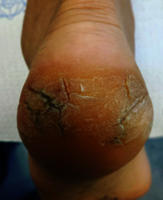

Dry skin can affect anyone but is more common with ageing, psoriasis, eczema, certain medical conditions, or as a side effect of some medications. Symptoms include skin roughness, itching, tightness, and cracking—particularly around the heel.

Fissures (cracks in the skin) may be superficial, affecting only the outer dead layers, or deep, involving the lower layers of the skin. Deep fissures often bleed and can be painful.